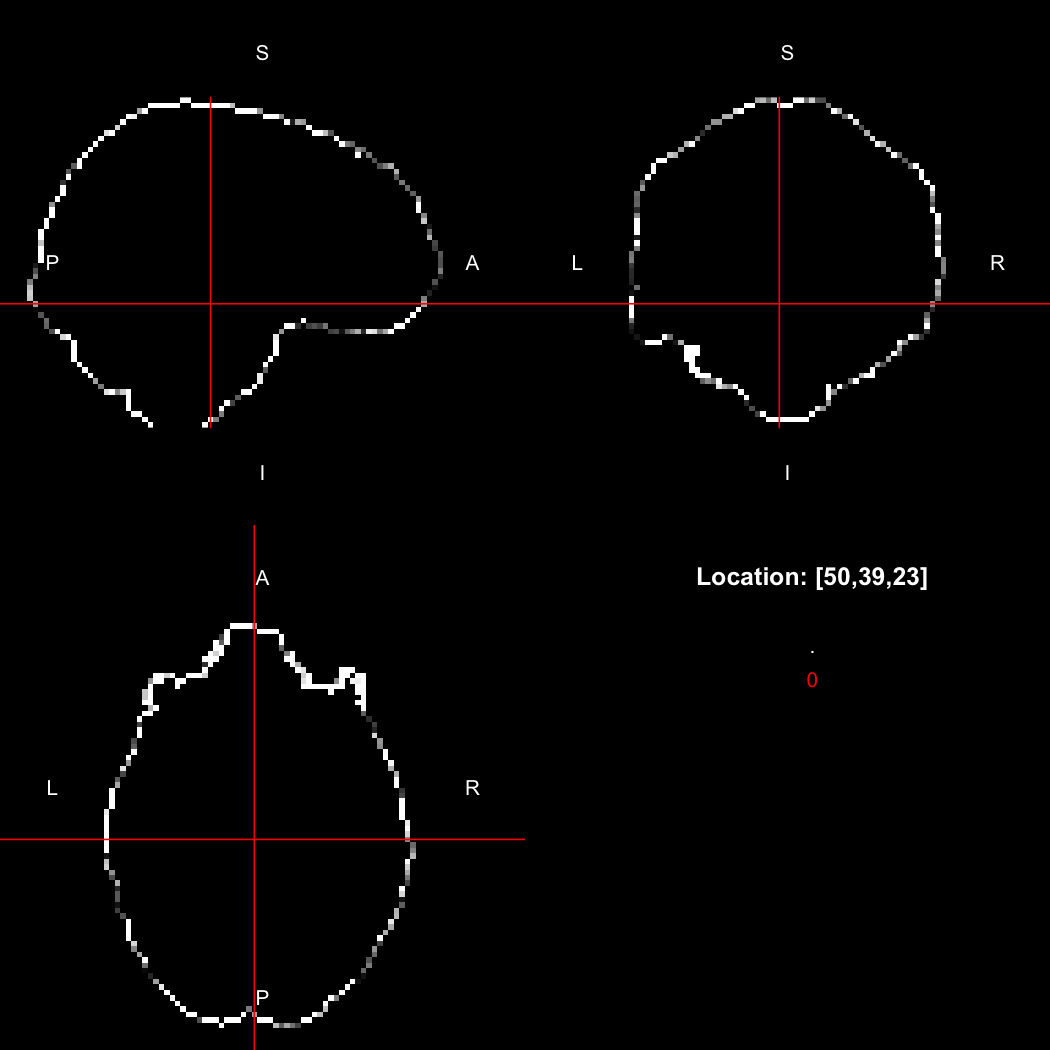

image %>% kernel_sphere(radius=3) %>% dilate() %>% subtract(image) %>% view()

## Setting window to (0, 60)

plot of chunk dilate

This example sets up a spherical kernel of radius 3 mm, dilates the image with it, and then subtracts the original image from the result to leave just the outer edge of the imaged object.